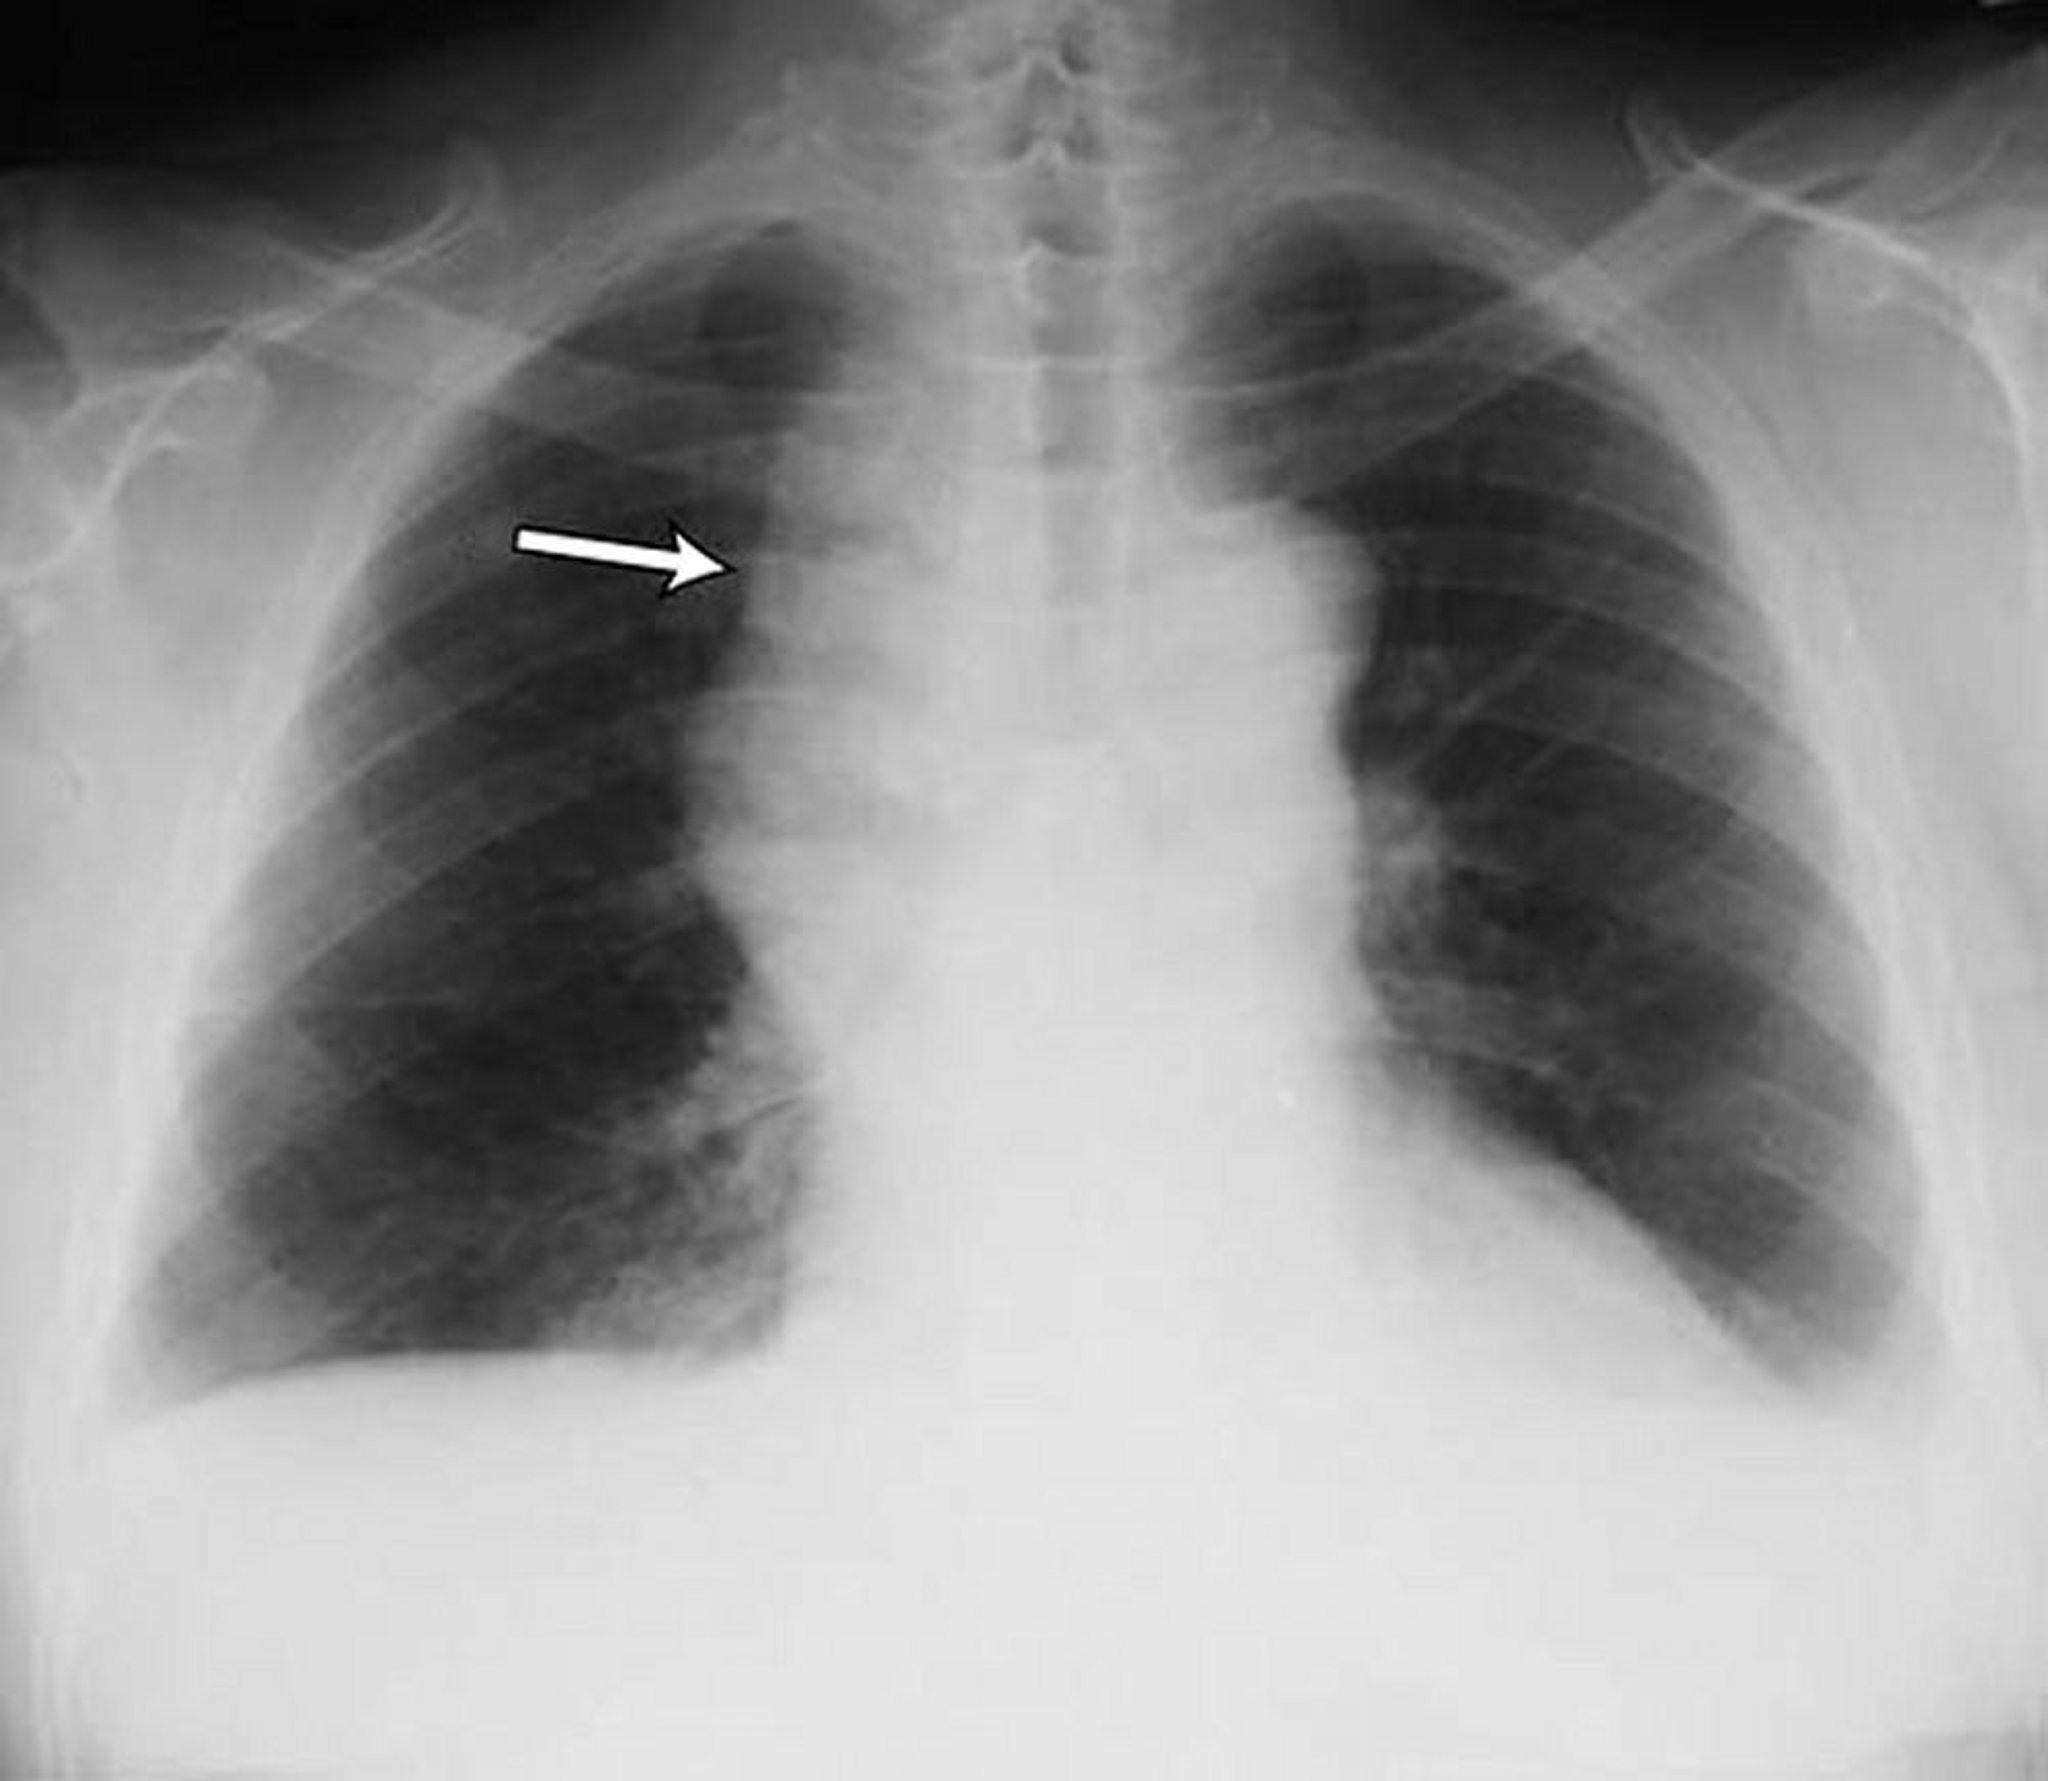

Small bilateral pleural effusions in a patient with non-Hodgkin lymphoma. Both costophrenic angles are blunted. The arrow points to widened mediastinum due to lymphoma.

By permission of the publisher. From Huggins J, Sahn S. In Bone's Atlas of Pulmonary and Critical Care Medicine. Edited by J Crapo. Philadelphia, Current Medicine, 2005.